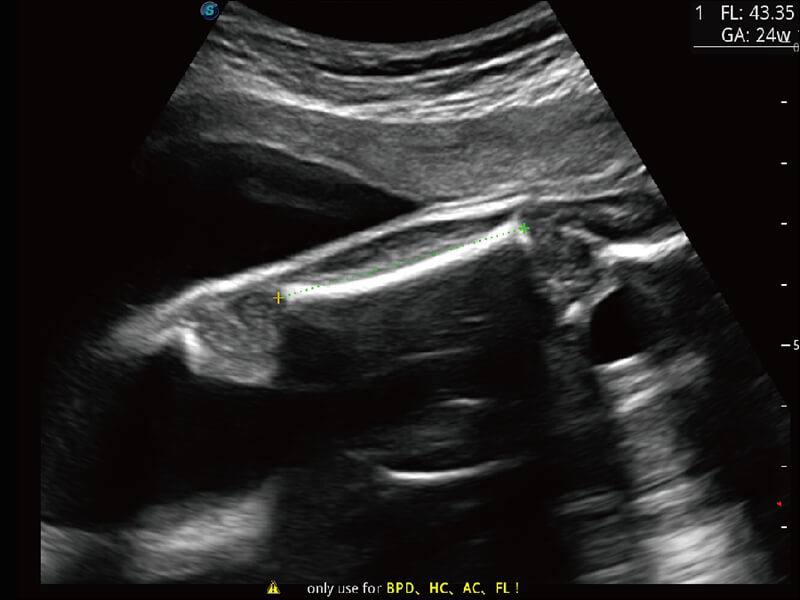

性能卓越的全新硬件架构,极大提升超声系统的运行效率和数据处理能力。相比以往超声成像系统,Wis+平台为您带来更快的响应速度和成像帧频,提升检查流畅度。

S60创新的探头工艺、高精度模数转换系统、前沿的波束重建技术,从前端信号处理每一个环节采集无损声学数据,真实还原组织原貌,再现解剖细节。